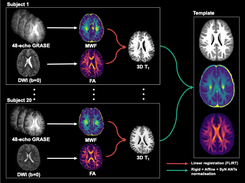

Atlas is described in this paper: https://onlinelibrary.wiley.com/doi/full/10.1111/jon.12689. Structural template, myelin water fraction, fractional anisotropy, mean diffusivity, radial diffusivity and axial diffusivity atlases for children aged 9-10 years are provided for free download for pediatric neuroimaging applications.